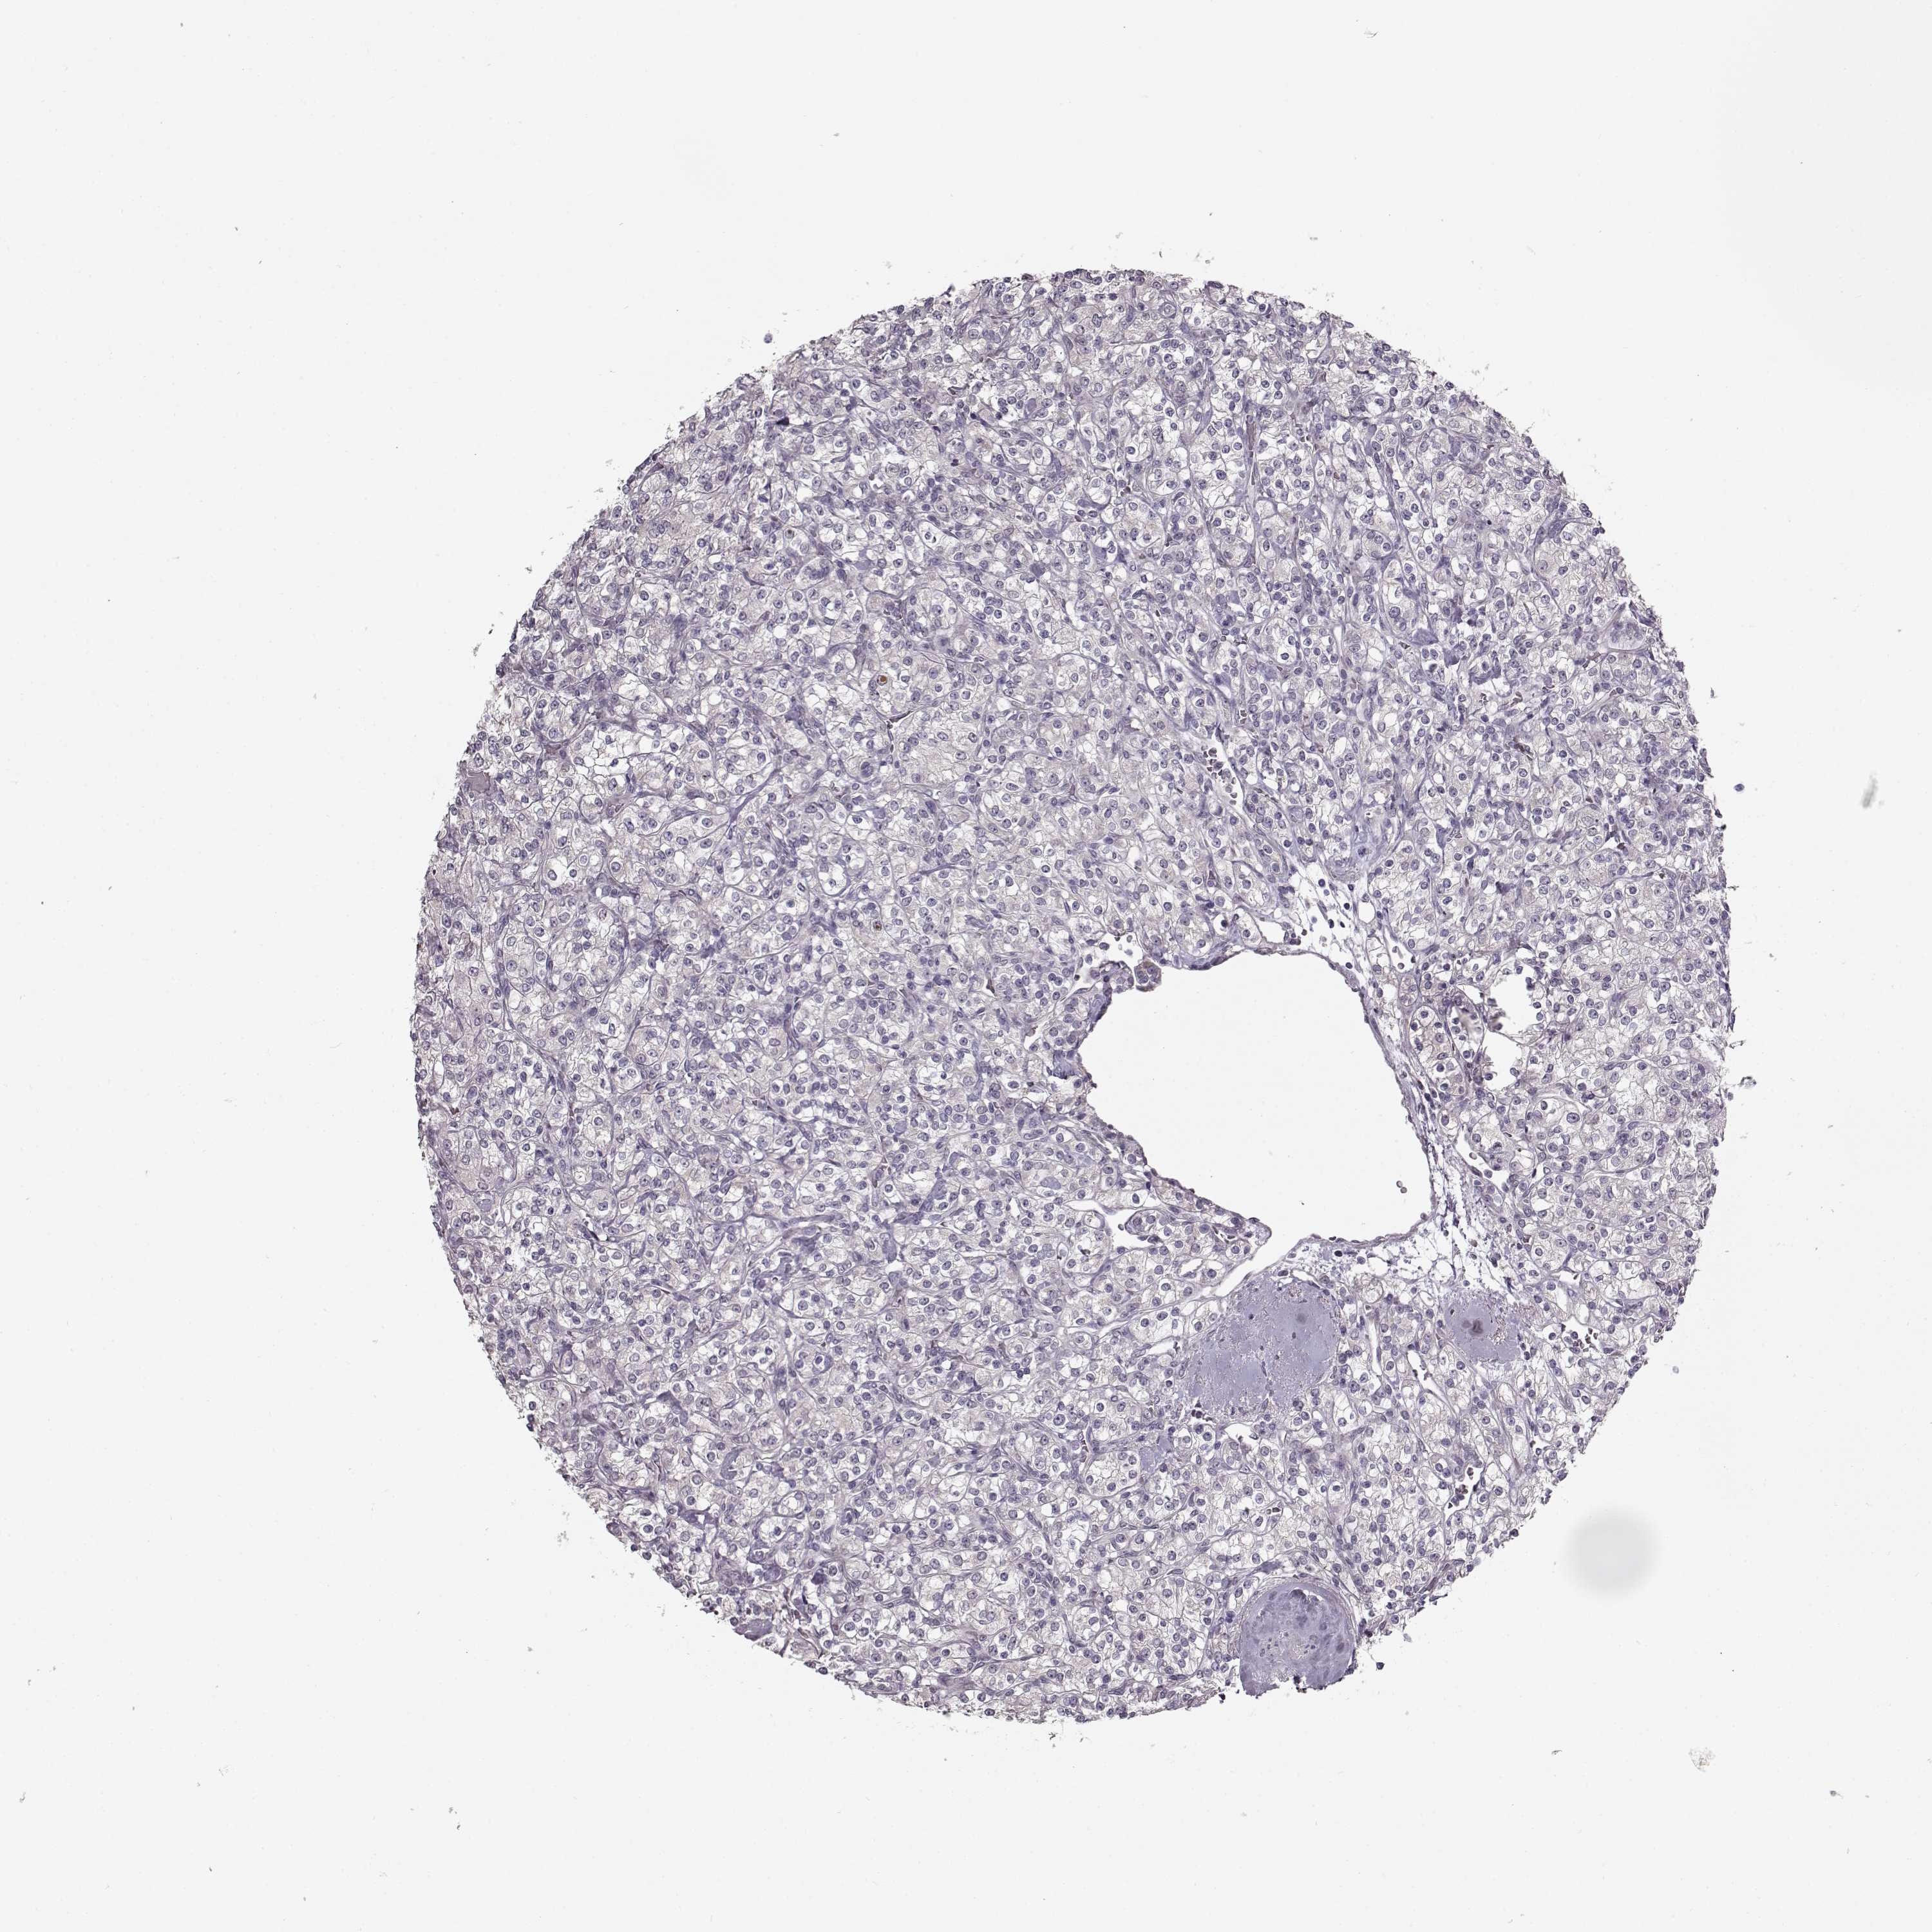

Kidney renal clear cell carcinoma

KIDNEY RENAL CLEAR CELL CARCINOMA (TCGA) - Interactive survival scatter ploti

The Survival Scatter plot shows the clinical status (i.e. dead or alive) for all individuals in the patient cohort, based on the same data that underlies the corresponding Kaplan-Meier plots. Patients that are alive at last time for follow-up are shown in blue and patients who have died during the study are shown in red.

The x-axis shows the expression levels (FPKM) of the investigated gene in the tumor tissue at the time of diagnosis. The y-axis shows the follow-up time after diagnosis (years). Both axes are complimented with kernel density curves demonstrating the data density over the axes. The top density plot shows the expression levels (FPKM) distribution among dead (red) and alive patients (blue). The right density plot shows the data density of the survived years of dead patients with high and low expression levels respectively, stratified using the cutoff indicated by the vertical dashed line through the Survival Scatter plot. This cutoff is automatically defined based on the FPKM cutoff that minimizes the p-score. The cutoff can be changed by dragging the vertical line or by entering a cutoff value in the square labeled "Current cut-off".

Under the Survival Scatter plot the p-score landscape (black curve; left axis) is shown together with dead median separation (red curve; right axis). Dead median separation is the difference in median mRNA expression between patients who have died with high and low expression, respectively. It is calculated as follows: median FPKM expression of dead patients with high expression - median FPKM expression of dead patients with low expression. This is intended to aid the user in visually exploring custom cutoffs and the associated p-scores and dead median separation.

Individual patient data is displayed and can be filtered by clicking on one or more of the category buttons on the top of the page. Categories describing expression level and patient information include: high, low, alive, dead, female, male and tumor stages. The scale of the x-axis can be toggled between linear and log-scale by clicking on the "x log" button. Mouse-over function shows TCGA ID, patient information and mRNA expression (FPKM) for each patient.

& Survival analysisi

Kaplan-Meier plots summarize results from analysis of correlation between mRNA expression level and patient survival. Patients were divided based on level of expression into one of the two groups "low" (under cut off) or "high" (over cut off). X-axis shows time for survival (years) and y-axis shows the probability of survival, where 1.0 corresponds to 100 percent.

MAP6D1 is not prognostic in Kidney Renal Clear Cell Carcinoma (TCGA)